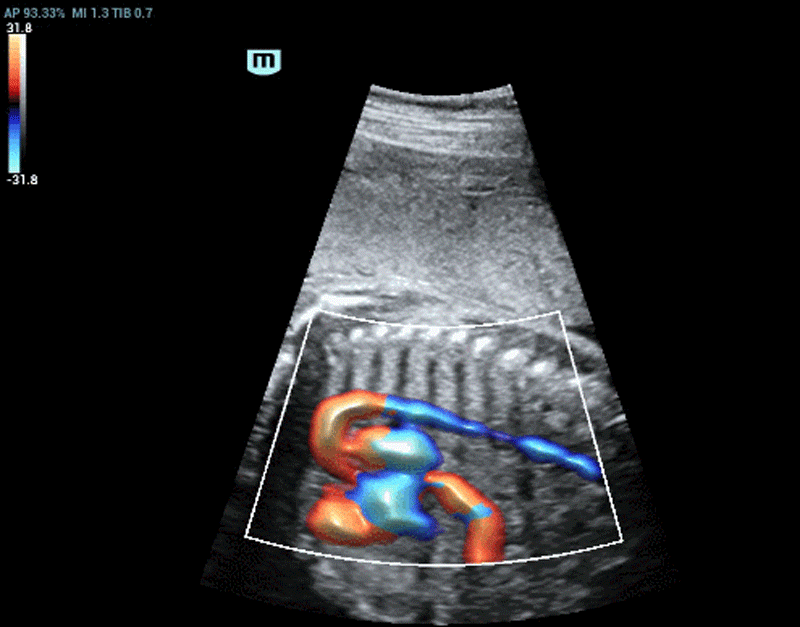

Moreover, the Glazing Flow indicates a breakthrough of color and power flow imaging which offers a brand new way to demonstrate the 2D color Doppler flow innovatively in a 3D visualization. It is able to provide intuitive and easy visualization of blood flow structures as well as boundary definition even for very tiny vessels which helps to achieve more clarity with less efforts. In this way, ultrasound users are able to acquire clear images within seconds even when they are fully zoomed in.

Varicocele with Glazing Flow